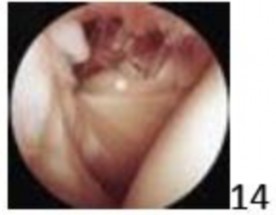

12. # Figure 14 shows the view looking forward from the posterosuperior portal during shoulder arthroscopy. The structure highlighted by the asterick is innervated by which of the following nerves?

DISCUSSION: The structure shown in the arthroscopic image is the tendon of the subscapularis muscle. The subscapularis muscle is innervated by the subscapular nerve. The subscapularis is not innervated by the other nerves listed.

The Preferred Response to Question # 14 is 2.